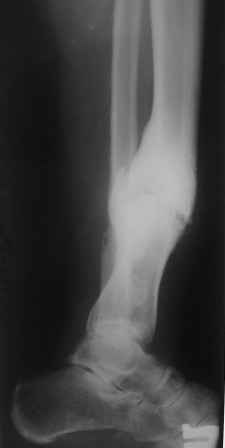

Больной 33г, лечится в течение 2-х лет, выходил на работу. Первоначально, был выполнен остеосинтез двумя шурупами с дополнительной фиксацией перелома наружной гипсовой повязкой. Снята преждевременно в поликлинике, через 3 месяца после операции, постепенно возникла варусно-рекурвационная деформация.Больному был наложен АВФ, с постепенной устранением деформации. Демонтаж АВФ через 4 месяца. Спустя 3 месяца появилась болезненность и стала нарастать деформация. В настояще время больной ходит с тростью, с полной нагрузкой на конечность. Имеется варусно-рекурвационная деформация 45-20 градусов. Болезненность при пальпации,незначительная подвижность в зоне перелома.

1. Наложить АВФ с остеотомией м/б кости, постепенное исправление деформации, после, БИОС.

2.Наложение АВФ с остеотомией в зоне ложного сустава, коррекция деформации- постепенная, после исправления осей- БИОС.

3.Открытая репозиция перелома, одномоментное устранение деформации, БИОС.